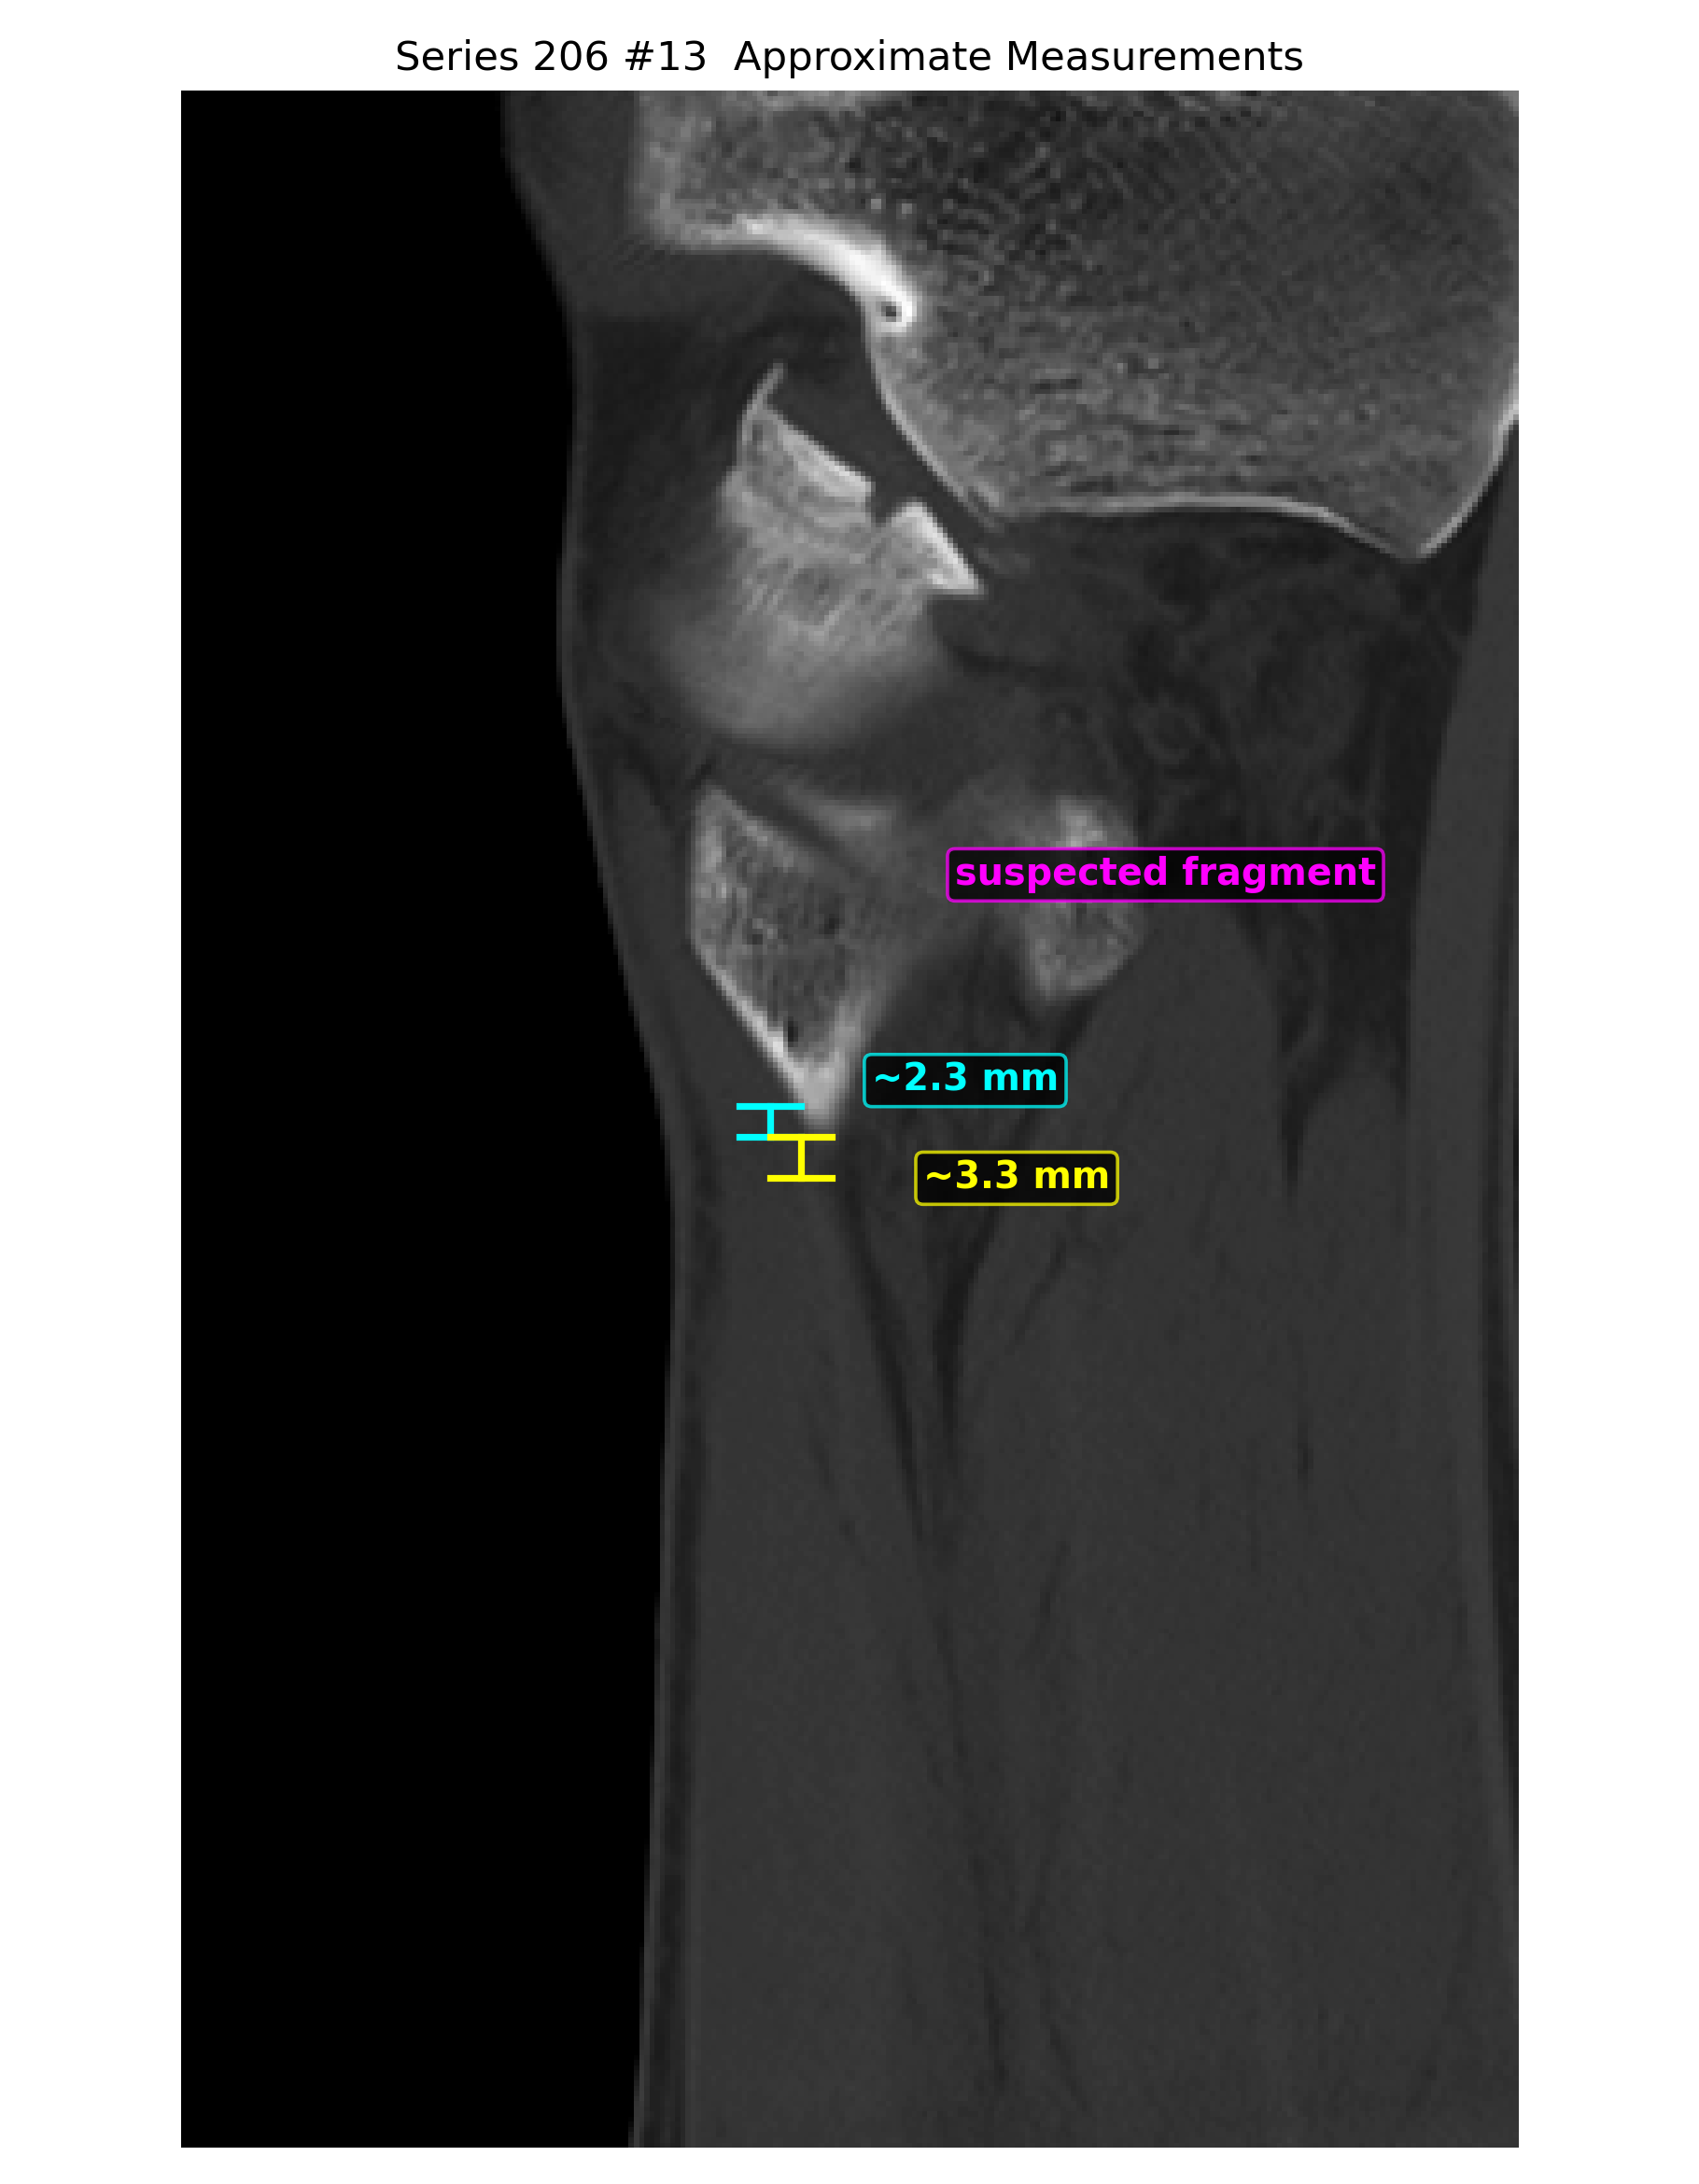

- 冠状位、矢状位和三维辅助重建里都能反复看到局部骨性不规则和分离感。

- 近似测量多次落在 2.0、2.3、2.8、3.3 mm 这个量级,支持轻度位移。

定量分析与标注图

以下毫米值为近似测量值,作用是帮助沟通位移量级,不等同于医生在工作站上的正式卡尺读数。

- 近似位移量级已经落在 2 到 3 mm 左右,值得认真评估手术阈值。